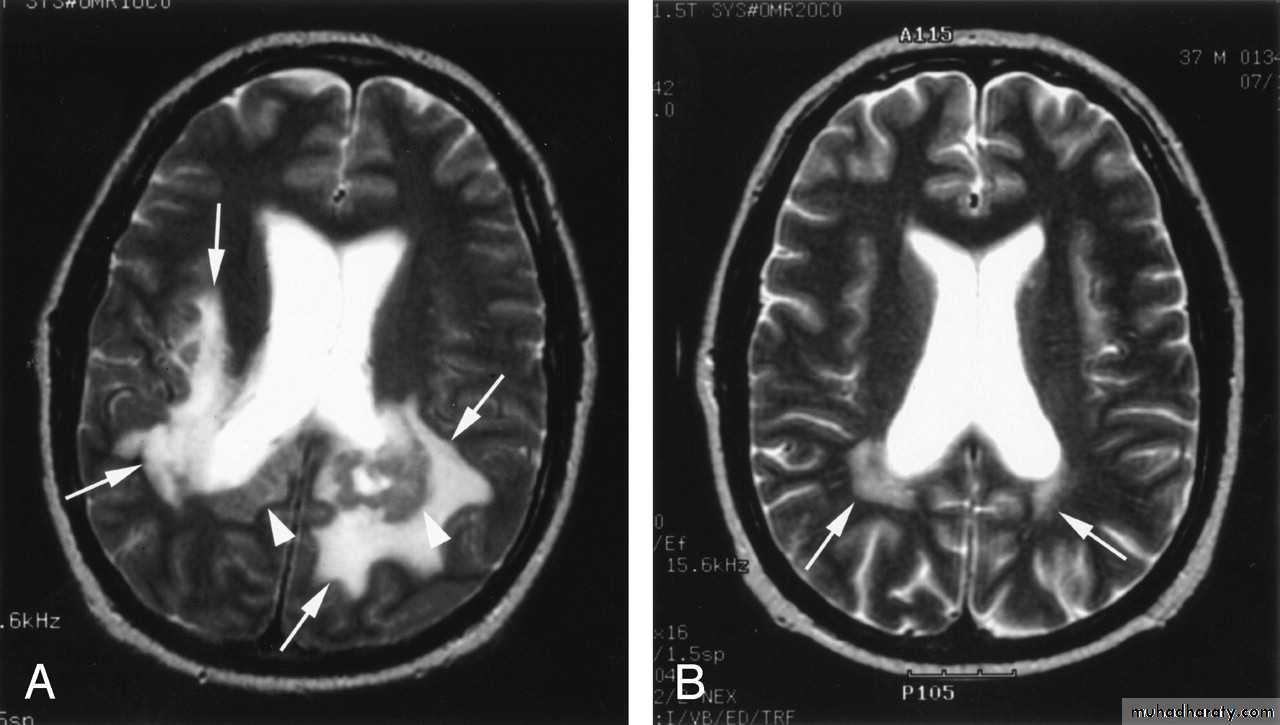

• Computed Tomography scan (CT scan) with/without contrast• Magnetic Resonance Imaging (MRI) with/without contrast